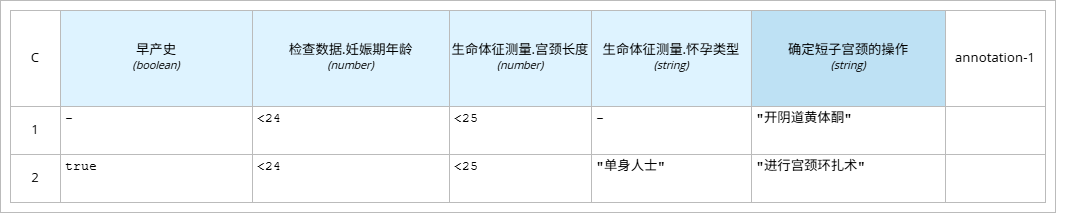

l “确定短子宫颈的操作”即通过“检查数据”、“生命体征测量”输入数据,以及“早产史”决策块来判断进一步的治疗措施。使用决策表的盒装结构。